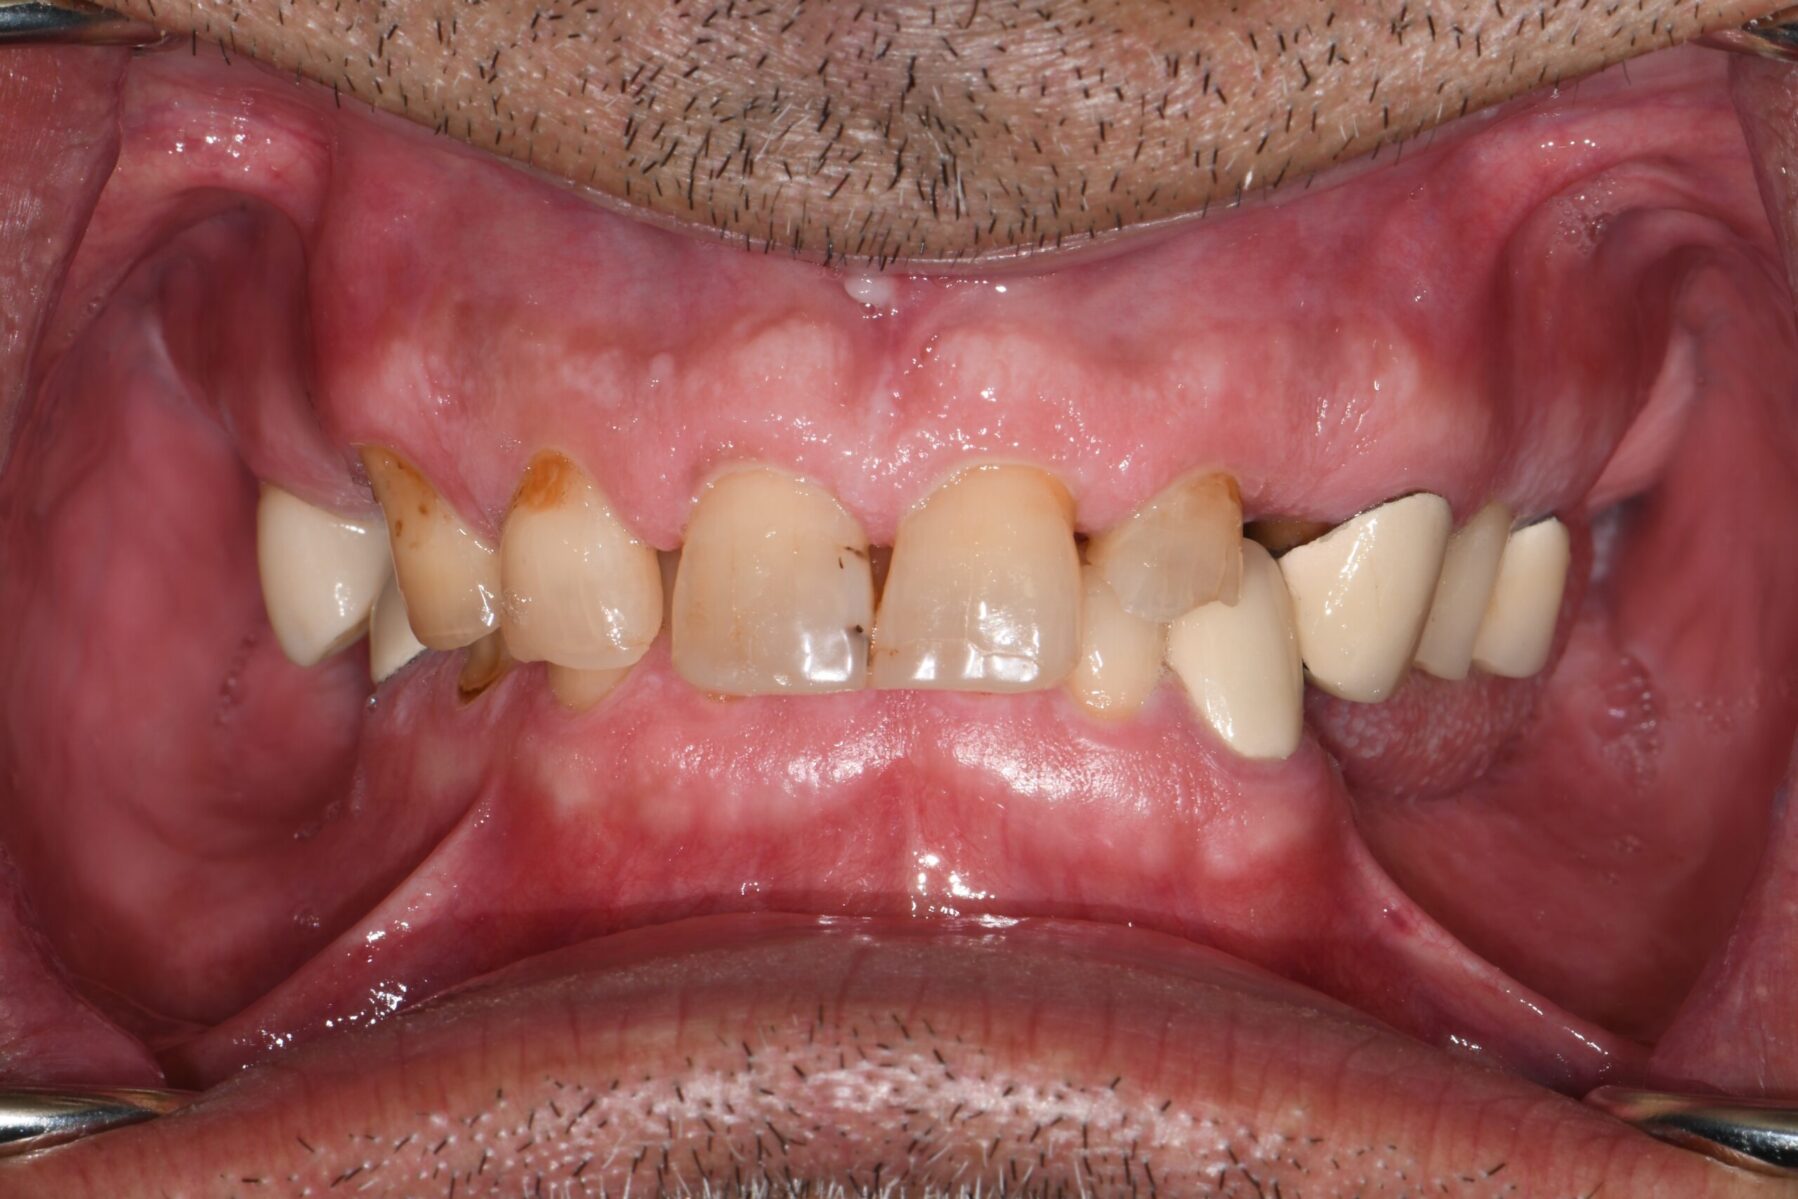

Full mouth rehabilitation encompasses a range of restorative dental procedures aimed at restoring the function, health, and esthetics of your entire mouth.

This may involve the use of crowns to protect and reinforce weakened teeth, dental implants to replace missing teeth, and veneers to improve the appearance of discolored or damaged teeth. Each treatment is tailored to match the color, shape, and size of your natural teeth, ensuring a cohesive and beautiful smile.

• Restoring multiple missing or damaged teeth for improved function and stability

• Restoring worn down teeth from grinding, clenching, or traumatic occlusion